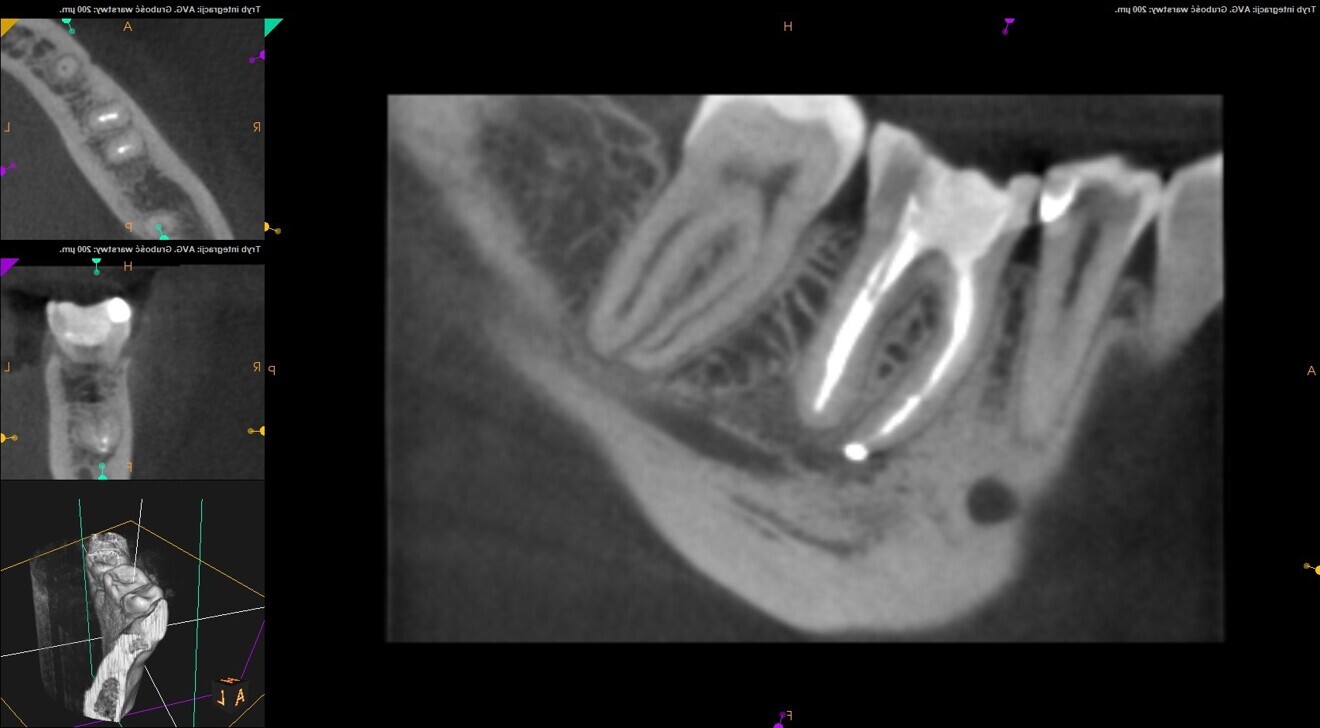

The patient came to the office because of moderate pain connected with the mandibular right first molar. A periapical radiograph and CBCT scan were performed. The images revealed radiolucency around the mesial root of the molar. Also, two pieces of a broken instrument were visible, one in the middle part of the root, before the curvature, and the other slightly below the curvature (Figs. 12 & 13).

After administering anaesthesia and placing a dental dam, the composite restoration was removed, and a temporary restoration with flowable composite and flowable dental dam for the root canal treatment was performed (Figs. 14–17). After removing the filling material from the mesiolingual and distal canals, access to the broken file was performed. The first piece of the instrument was removed with the ultrasonic tip (Fig. 18), and the tip of the second piece of the file then became visible. Unfortunately, the removed file piece broke in the middle and only the coronal part could be retrieved (Fig. 19). Because the apical part of the broken file was invisible and did not emerge from the canal during the irrigation and activation, an attempt at bypassing it was made. Analysis of the CBCT scan did not reveal a clear answer as to whether there was one apical foramen, so during the bypass procedure through the mesiolingual canal, a periapical radiograph was performed. The radiograph indicated that either there was a ledge in the apical area or there were two separate apical foramina (Fig. 20). For the irrigation protocol, the AutoSWEEPS mode was used at 1.2 W power with the flat SWEEPS 300/20 fibre tip. The tips of both mesial canals were placed below the orifice. The Less-Prep Endo protocol was performed twice in the manner described elsewhere.5 After the irrigation, irrigant flow between both canals was rapid.

The canals were dried with paper points and micro-suction (Fig. 21). After the irrigation protocol, there was still a lack of patency and tugback was achieved only in the mesiolingual canal. The mesiobuccal and distal canals were filled with an epoxy resin sealer and warm gutta-percha (squirting technique), and the mesiolingual canal was filled with a 30/.04 gutta-percha cone with the continuous wave of condensation technique (Fig. 22). A distally shifted periapical radiograph was performed (Fig. 23). The radiograph revealed a puff of sealer in the periapical area of the mesial root and the isthmus filled with the sealing material. A composite material was placed into the access cavity, and the patient was scheduled for the control appointment. At six months and 12 months, CBCT scans were performed (Figs. 24 & 25). The images found no signs of inflammation in the periapical area, and the tooth was asymptomatic.

Fig. 24: CBCT scan at the six-month follow-up.

Fig. 25: CBCT scan at the 12-month follow-up.